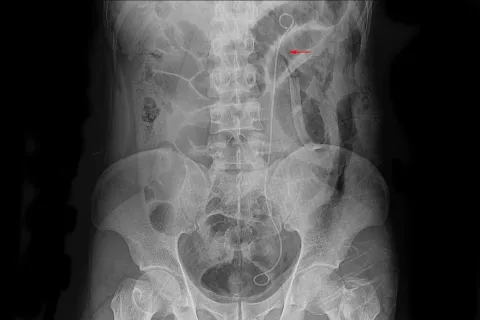

Ureteral stents are an implant used to correct a blockage in one of the ureters in your body. The ureters are... Read More